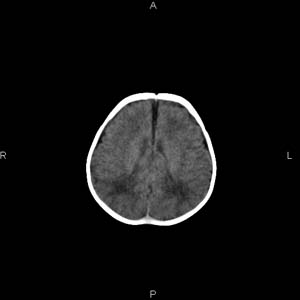

患者男,27天,出生后正常,今天中午在母亲怀里抱着吃奶在放下睡觉时发现后枕部慢慢出现一包块,来查头颅ct。无外伤史。包块内ct值47-51hu。请大家讨论。

支持脑膜脑膨出,双侧侧脑室三角区周围脑白质对称性低密度影,考虑缺血缺氧性脑病或肾上腺性脑白质营养不良。

\"中午在母亲怀里抱着吃奶在放下睡觉时发现后枕部慢慢出现一包块,包块内ct值47-51hu。

颅骨无缺损,骨缝无增宽.支持头皮血肿(血管破裂)